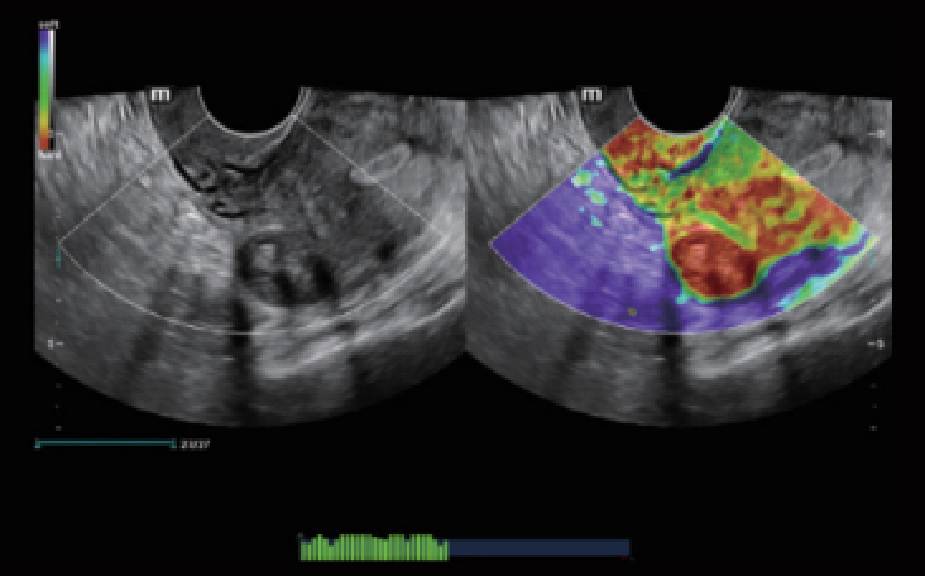

Platform ZST+ merupakan inovasi luar biasa yang mewakili evolusi ultrasound. Mentransformasikan metrik ultrasound dari pembentukan cahaya konvensional menjadi pemrosesan berbasis channel data. Mengatasi batasan kompromi tradisional antara resolusi spasial, resolusi temporal, dan keseragaman jaringan, menghadirkan mutu gambar yang luar biasa untuk solusi pencitraan tak terbatas dengan peningkatan secara berkelanjutan.

Gambar Klinis